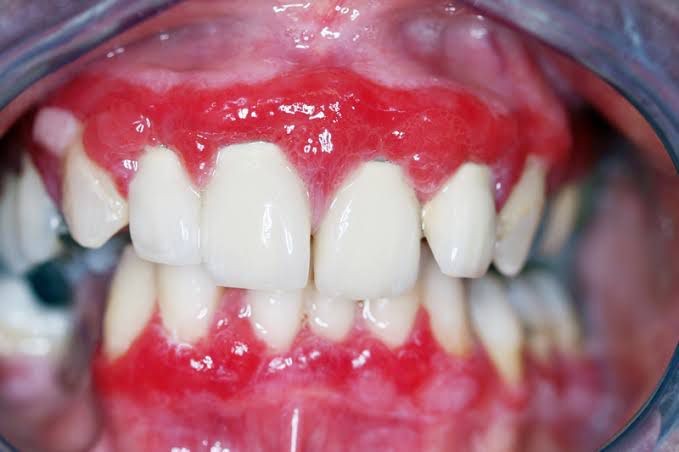

Mucous membrane pemphigoid (MMP) is a heterogeneous group of chronic, autoimmune subepithelial blistering diseases which is characterized by blistering lesions that primarily affect the various mucous membranes of the body. Oral mucosa, the site of most frequent involvement, often does not show evidence of scarring. Desquamative gingivitis which is the friability of gingiva with erosions, is a common finding at the interdental papillae. However, erosions can occur throughout the oropharyngeal mucosa. Ophthalmic involvement is also common. Therefore, even if patients do not complain of eye symptoms, the conjunctiva should be examined. Any signs of conjuntival erythema and inflammation should be further evaluated by an ophthalmologist. By: https://www.dermatologyadvisor.com/home/decision-support-in-medicine/dermatology/mucous-membrane-pemphigoid-mucous-membrane-cicatricial-pemphigoid-cicatricial-pemphigoid-anti-epiligrin-cicatricial-pemphigoid-benign-mucous-membrane-pemphigoid-benign-mucosal-pemphigoid/